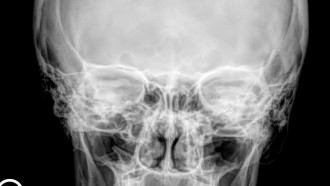

Densytometria jest najlepszą dostępną metodą diagnozowania osteoporozy, również w jej stadium bezobjawowym, czyli przed wystąpieniem złamania kości lub kręgosłupa. Służy także ocenie efektywności prowadzonego leczenia. Jest to rodzaj badania wykorzystującego niewielkie dawki promieniowania rentgenowskiego i ma na celu określenie gęstości mineralnej kości (BMD - Bone Mineral Denstity)

Wynik badania jest podawany w g/cm2 i określa gęstość tkanki kostnej w ocenianym obszarze. W diagnostyce osteoporozy największym znaczeniem klinicznym charakteryzuje się densytometria kręgosłupa lędźwiowego oraz densytometria szyjki kości udowej. W oparciu o wartości wskaźnika T, WHO opracowało kategorie diagnostyczne osteoporozy. Wartość wskaźnika od +1 do -1.0 oznacza normę, pomiędzy -1.1 a -2.4 osteopenię, a od -2,5 lub mniej osteoporozę. Wyniki badań dostępne są na stronie multidiagnostica.lab-online.pl